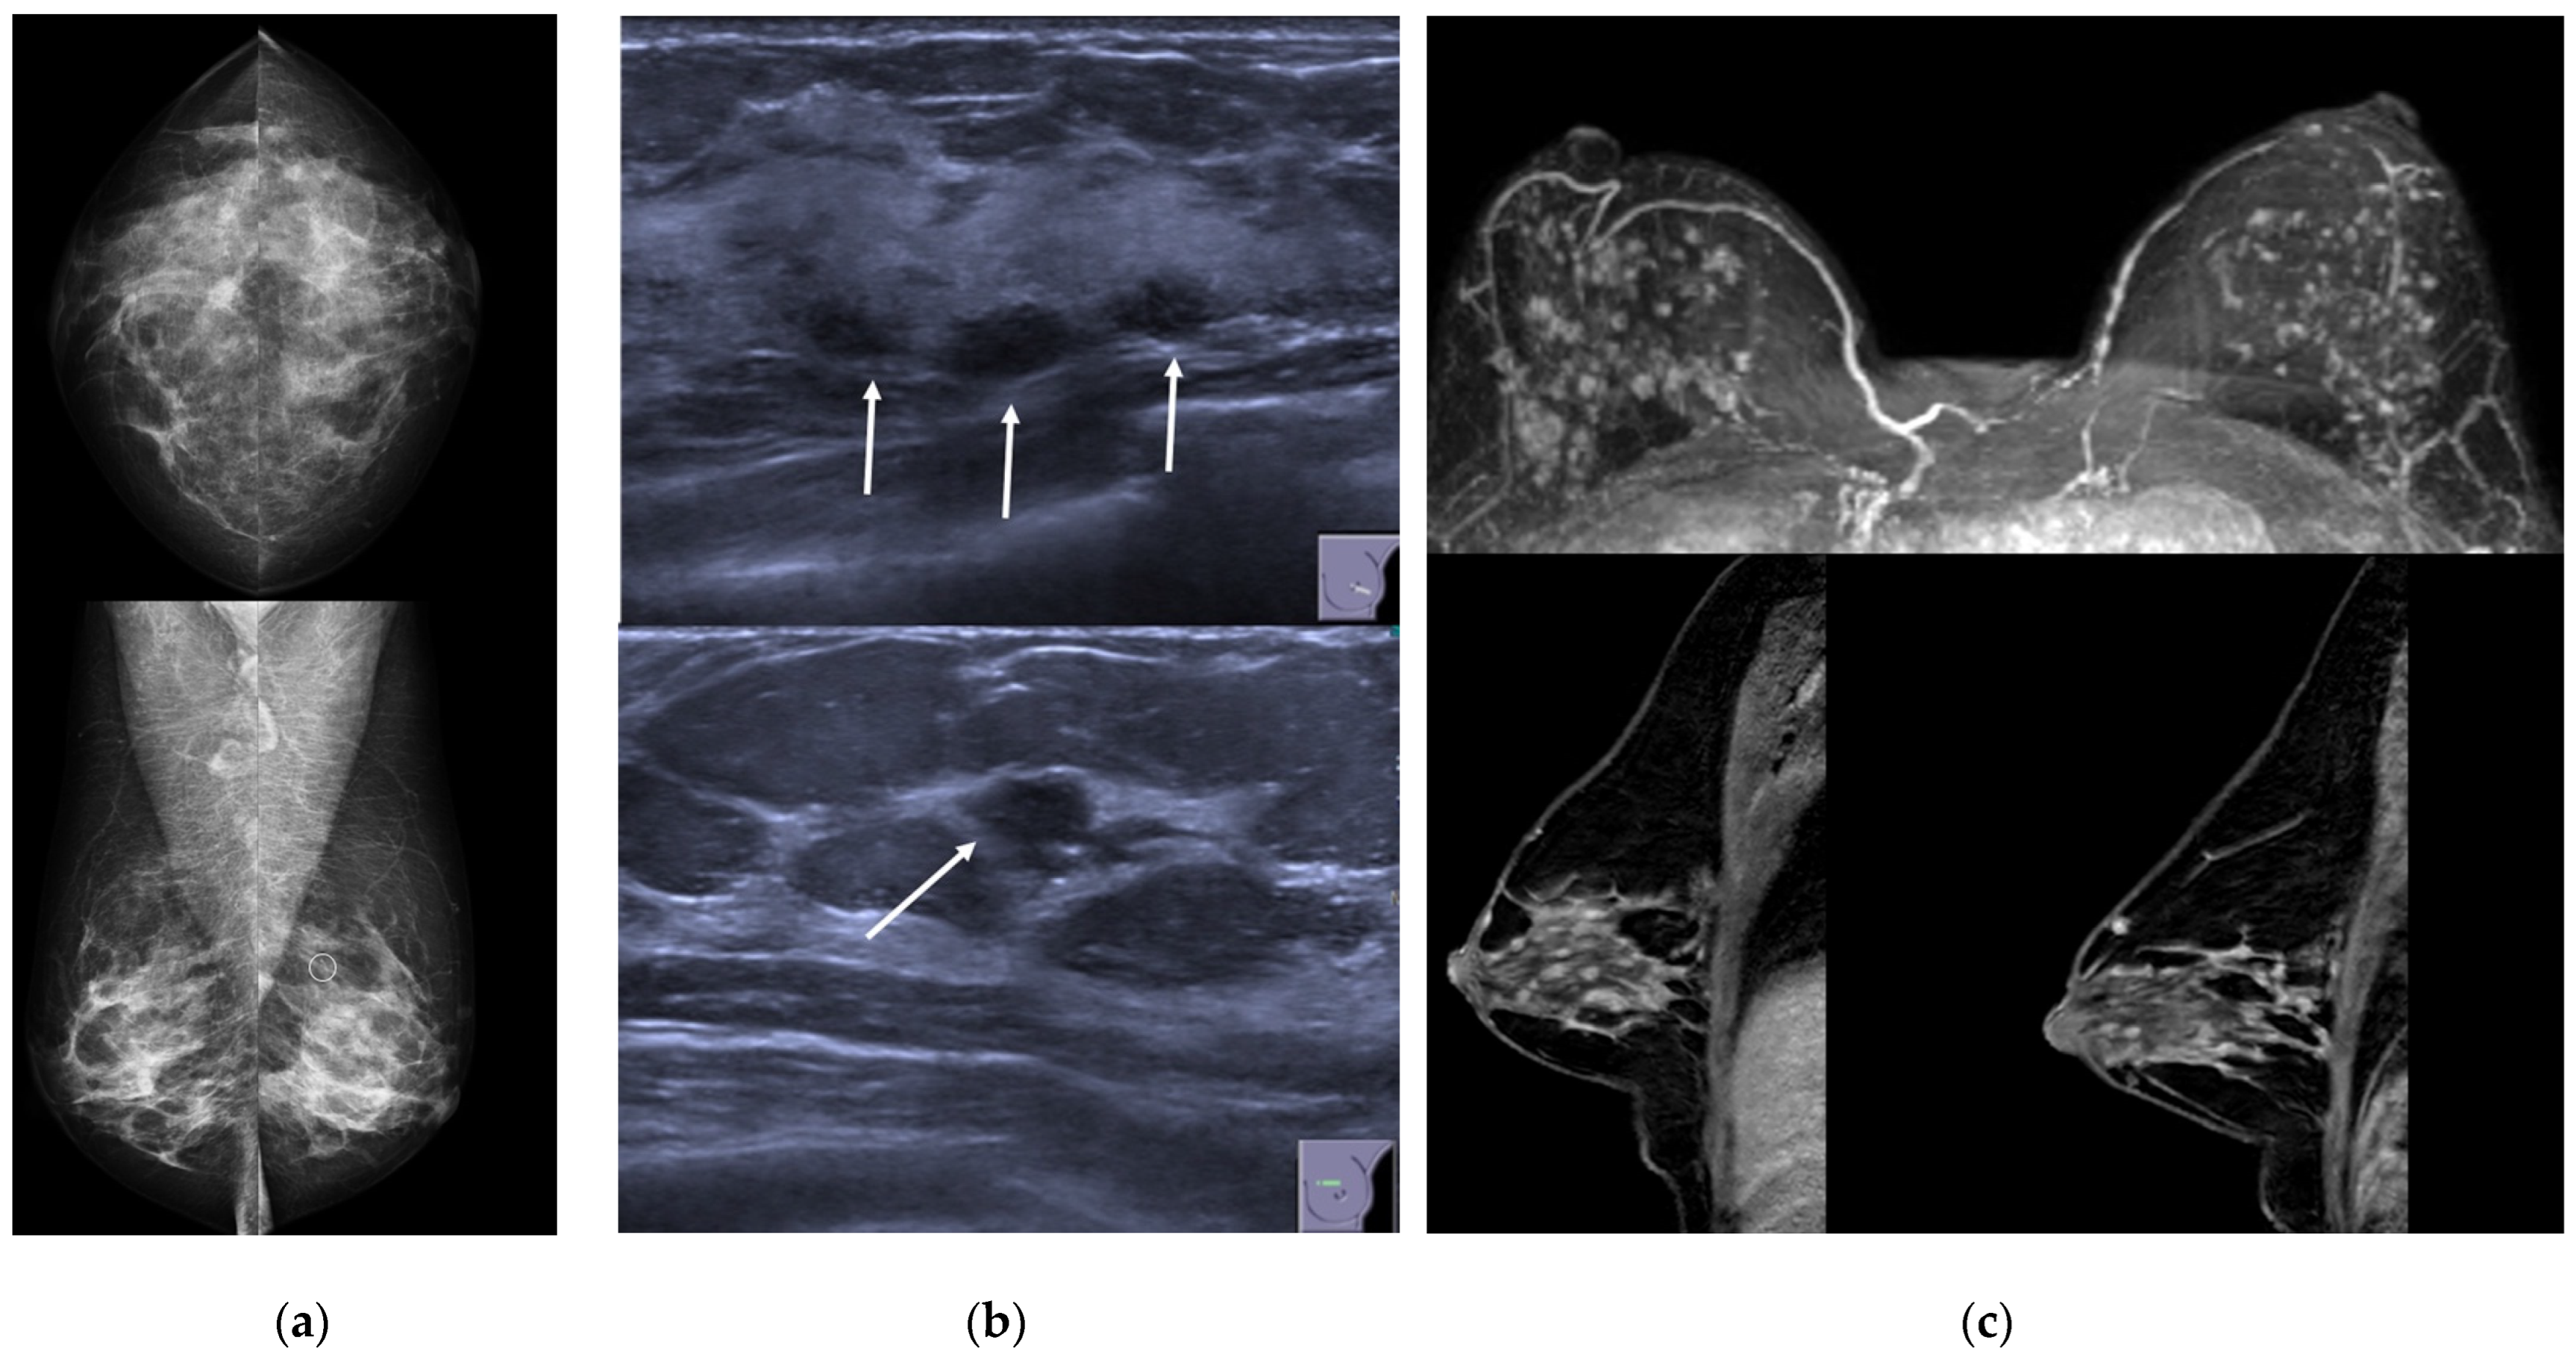

| Son 2009 [25] | Retrospective cohort, patients who underwent surgery due to papillomas of the breast and performed 3D fast low-angle shot (FLASH) dynamic breast MRI | NR | 3 | 41.7 ± 12.9 (27–51) | 2/3 palpable mass, 1/3 bloody nipple discharge | MX: 2/3 microcalcifications US: 3/3 multiple masses MRI: 1/3 multiple nodular enhancement; 1 ductal non-mass enhancement, 1 segmental non-mass enhancement | NR | NR | NR | |

| Sarica 2018 [26] | Retrospective cohort, patients with a pathologic diagnosis of papillary lesion who performed MRI and US | NR | 11 | 41.45 ± 7.7 | 1/11 palpable mass, 3/11 unilateral nipple discharge | US: 3/11 dilated duct partially/completely filled with intraluminal content; 1/11 mass with ductal relation or intracystic mass; 6/11 heterogeneous tubular nonmass-like hypoechoic area or mass related to multiple dilated ducts; 1/11 occult MRI: 3/11 dilated duct and intraductal focal mass on T2; 2/11 Dilated duct and pre-contrast high T1 signal; 2/11 mass with crescentic peripheral fluid; 3/11 mass related with dilated duct-ductal contrast enhancement; 1/11 linear-ductal contrast enhancement; 3/11 segmental contrast enhancement | NR | NR | NR | |